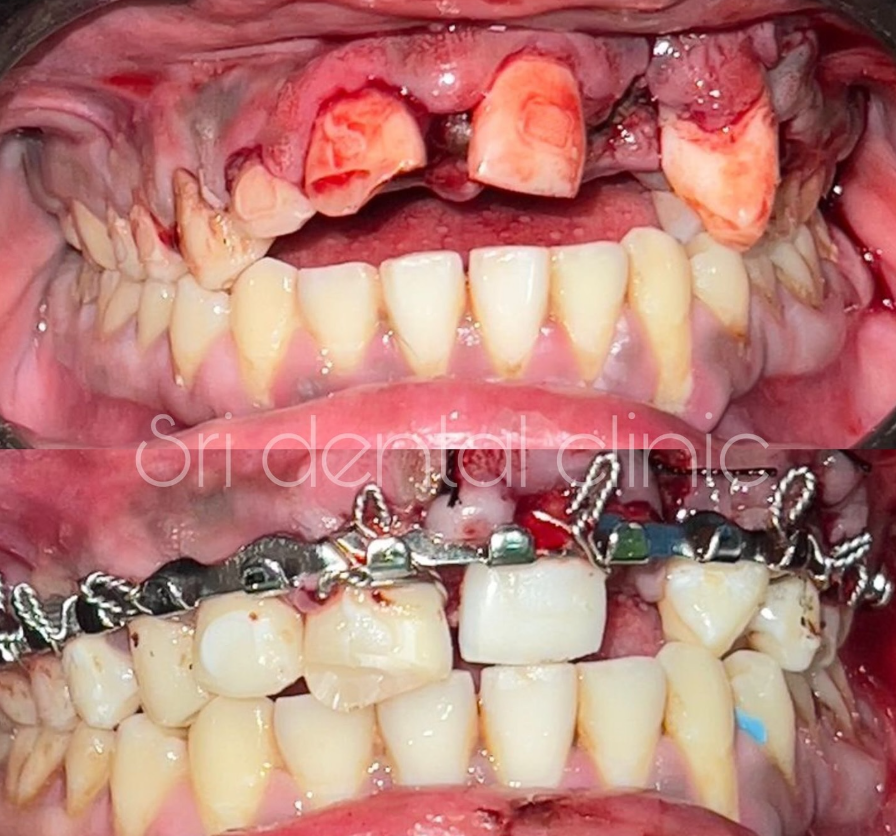

A Jaw Fracture (mandible or maxilla fracture) is a break in one of the jaw bones caused by injury, accidents, sports trauma, or falls. Early diagnosis and proper treatment are crucial to prevent complications like infection, bite issues, or difficulty in jaw movement.

Treatment depends on the severity and location of the fracture:

Closed Reduction

Open Reduction & Internal Fixation (ORIF)

Intermaxillary Fixation (IMF)

Post-Trauma Reconstruction